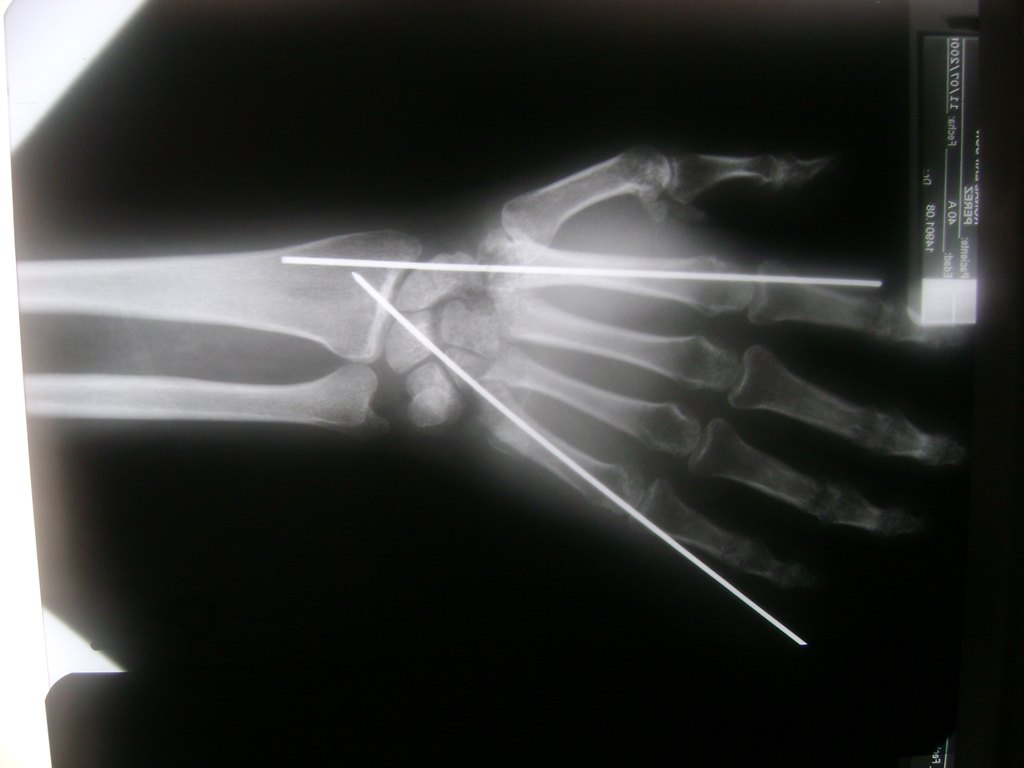

Cirugías de Codo - Cirugías de Muñecas y Manos

Los procedimientos más comunes en cirugía de la mano son aquellos destinados a reparar traumatismos, incluyendo lesiones de tendones, nervios, vasos sanguíneos, y articulaciones; huesos fracturados; y quemaduras, cortes, y otros daños de la piel.